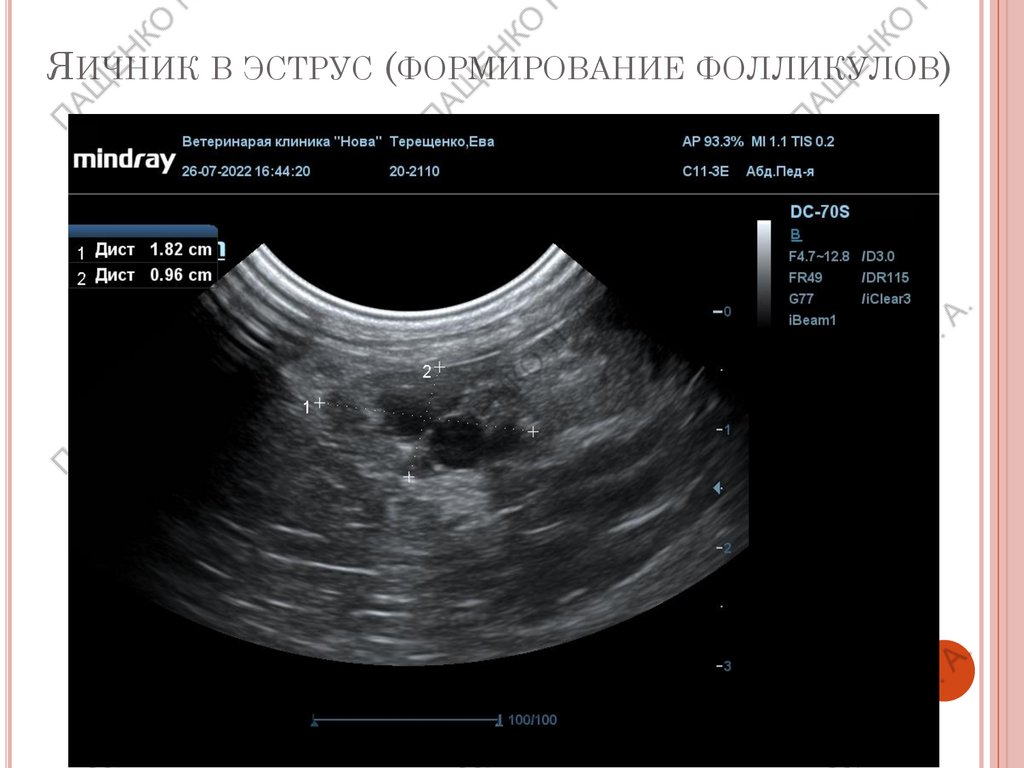

ЯИЧНИК В ЭСТРУС (ФОРМИРОВАНИЕ ФОЛЛИКУЛОВ)

В проэструс размер увеличивается, контуры становятся

бугристыми, появляются фолликулы с тонкими стенками,

размер зависит от породы, за сутки до овуляции размер

фолликулов от 0,5 до 1,1 см.